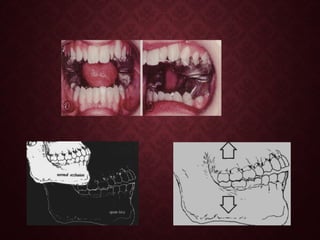

Surgical procedure:-Surgical procedure:-

Palatal approach was used to expose the

maxillary canine.

Vertical magnetic bracket bonded on the palatal

crown surface of the impacted canine.

• A spacer of 2.5mm is positioned between the magnetic bracket &

loose intraoral magnet.

•Fixation of the intraoral magnet to the Hawley type retainer with self

curing acrylic followed by removal of spacer , to apply an attraction force

of 0.3N.

•Treatment progression of the magnetic attraction

after 3 months.

• Fixed appliance treatment stage.